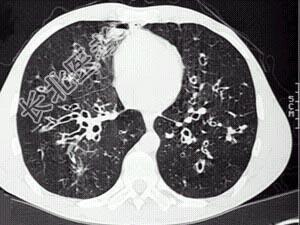

- 单项选择题女,36岁, 咳嗽,咳痰, 咯血,反复发作, CT检查如图,应诊断为 ( )

A、双下肺支气管扩张并感染

B、多发性肺囊肿并感染

C、双下肺肺包虫病

D、间质性肺炎

E、肺气肿